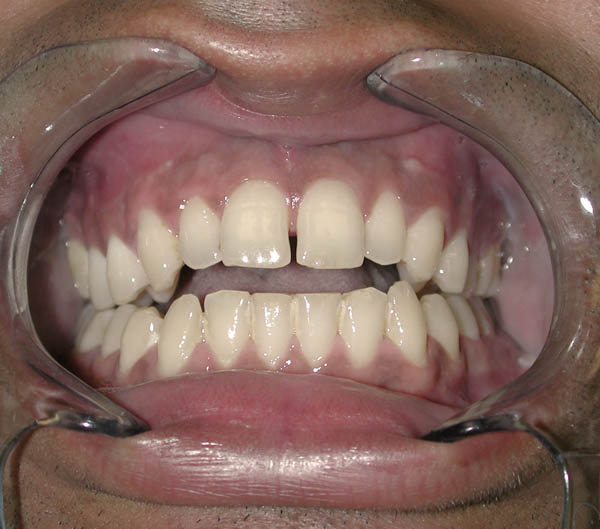

Gap Between Front Teeth : Anterior Open Bite